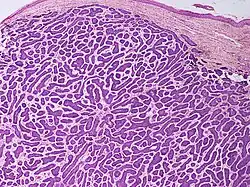

Basal-cell carcinoma cells resemble epidermal basal cells and are usually well differentiated.[27]

Nodular basal-cell carcinoma (also known as "classic basal-cell carcinoma") accounts for 50% of all BCC.[29] It most commonly occurs on the sun-exposed areas of the head and neck.[30]: 748 [31]: 646 Histopathology shows aggregates of basaloid cells with well-defined borders, showing a peripheral palisading of cells and one or more typical clefts.[29] Such clefts are caused by shrinkage of mucin during tissue fixation and staining.[32] Central necrosis with eosinophilic, granular features may also be present, as well as mucin. The heavy aggregates of mucin determine a cystic structure. Calcification may also be present, especially in long-standing lesions.[29] Mitotic activity is usually not so evident, but a high mitotic rate may be present in more aggressive lesions.[29] Adenoidal BCC can be classified as a variant of NBCC, characterized by basaloid cells with a reticulated configuration extending into the dermis.[29]